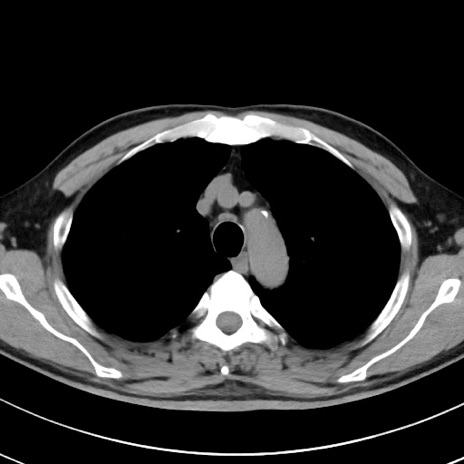

【腹部TIPS】症例29 参考症例 CT(横断像)

症例

70歳代男性